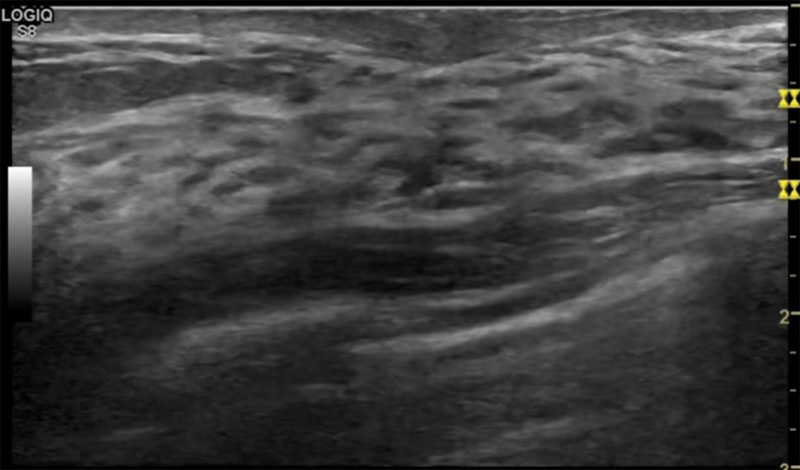

乳房脹痛,觸摸疼痛,手摸起來感覺有腫塊。這個是什么問題呢?醫(yī)生診斷一般是乳腺增生。那么在乳腺超聲設(shè)備檢查后,報告單卻顯示雙乳未見明顯占位性病變。乳腺增生是很多女性,特別是育齡期女性都有的經(jīng)歷、到底乳腺增生癥狀有哪些?會給我們帶來怎樣的影響呢?乳腺增生不是腫瘤跟炎癥。乳腺組織增生及退行性變跟內(nèi)分泌功能紊亂有關(guān)系。正常的生理改變。還有乳腺病,良性乳腺結(jié)構(gòu)不良等名稱。

乳腺增生有什么癥狀,病因?比較典型的就是乳房疼痛,特別是經(jīng)前癥狀比較重,經(jīng)后就有所緩解。有時候還能碰到乳房硬塊。根據(jù)經(jīng)期的變化而變化硬度大小都有變。乳腺在內(nèi)分泌激素,伴隨月經(jīng)周期有增生問題。內(nèi)分泌激素代謝失衡,雌激素水平增高,出現(xiàn)乳腺組織增生過度,增生組織不退的情況下,就會有乳腺增生癥狀。這個不會增加乳腺癌的風(fēng)險。所以不用緊張的。不過乳腺癌的病人都會有乳腺增生。所以乳腺增長有沒癥狀,都需要進(jìn)行常規(guī)的體檢。